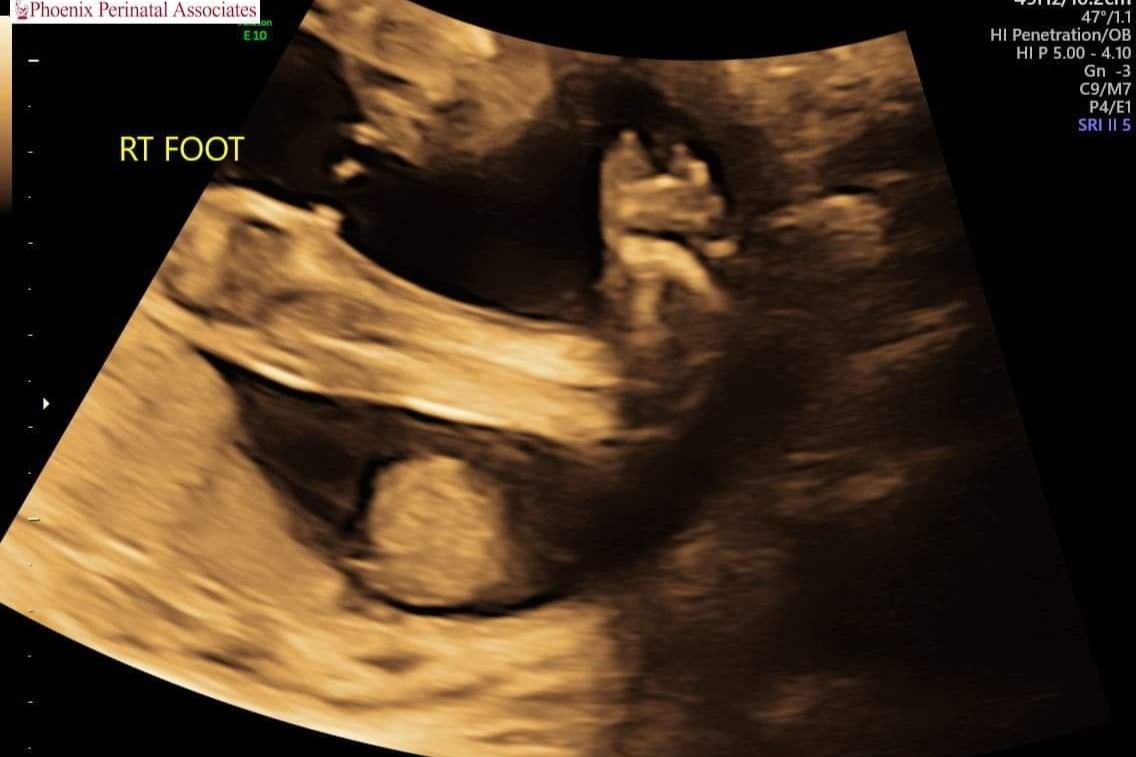

On Tuesday May 11th 2021 our family received fateful news that any expecting parent dreads hearing: our baby has a birth defect. Spina bifida myelomeningocele, a rare neural tube defect that causes baby's spine to not fuse properly which results in their spinal cord, nerves, and spinal fluid to pool outside of the spinal column. Common issues with this include paralysis, ambulatory, and developmental difficulties.